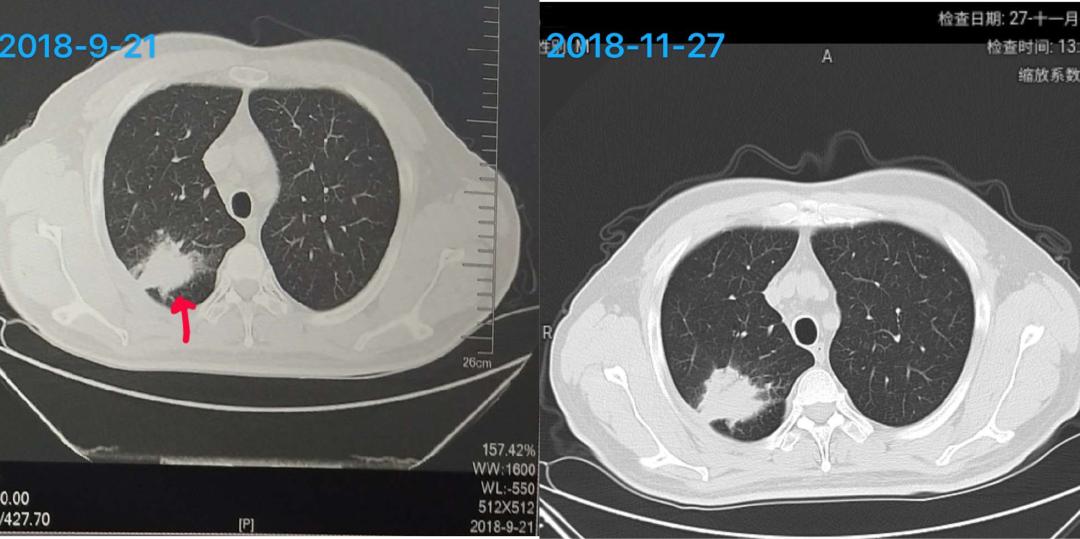

Vv爸爸2018年9月21日,免疫治疗原发灶基线46mm*27mm,用药2个月后,2018年11月27日第一次CT影像评估 51mm*42mm,肿瘤明显增大,医生怀疑我家打化肥了。。。啰嗦一句,为什么肿内科一旦看到病灶大了就提化肥呢?好几个专家都跟我提过“化肥”,一度让我怀疑自己是进了农科院。

接着看下图,用药3个月后,2019年1月评估37mm×26mm,用药4个月后,2019年2月评估21mm*19mm,病灶持续缩小。